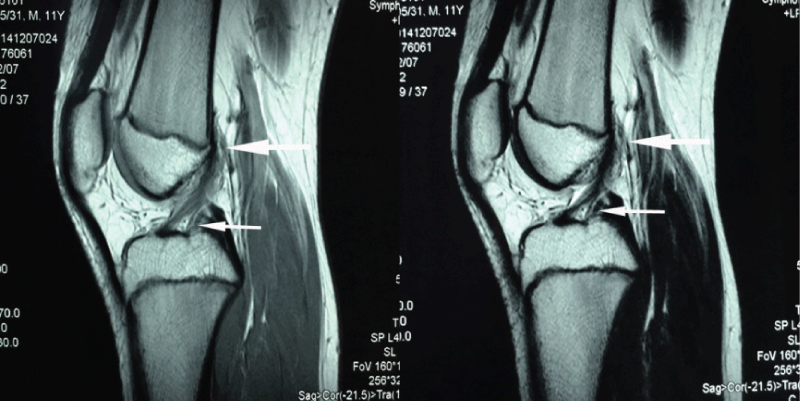

The MRI of ACL/PCL normal knee joint is shown in figure 1, 2, 3. The normal knee joint study group of 203 patients consisted of 137 men (67.5%) and 66 women (32.5%), and average age was 13.5 years (range: 8 - 15 years). The knee composite of the femur, tibia, ACL and PCL, and epiphyseal plate were shown clearly. The ACL finds its origin from epiphyseal plate on the medial surface of the lateral femoral condyle, runs an oblique course within the knee joint and inserts into the central tibial plateau (Figure 1).

Figure 1: MR images (sagittal view) of the ACL originate (big arrow) and terminate (small arrow). The big arrow indicates the ligament directed originate from the epiphyseal plate, and the small arrow indicates the ligament terminated the bone which it attachment.

The PCL arises from a depression posterior to the intraarticular upper surface of the tibia epiphyseal plate and courses anteromedially behind the ACL and inserts into the medial femoral condyle (Figure 2).

Figure 2: MR images (sagittal view) of the PCL originate (big arrow) and terminate (small arrow). The big arrow indicates the ligament directed originate from the epiphyseal plate, and the small arrow indicates the ligament terminated the bone which it attachment.

It's very clear that the ACL/PCL originated in the epiphyseal plate of distal femur and proximal tibia, and terminates in the tibia and femur by a fibrous ligament tissue directly grown into the bone tissue (Figure 3). However, there were no fibrous ligament tissue directly grown into the originate bone of ACL/PCL in femur and tibia.

Figure 3: MR images (sagittal view) of the ACL (A) and PCL (B) originates (big arrows) and terminates (small arrows). The big arrow indicates the ligament directed originate from the epiphyseal plate, and the small arrow indicates the ligament terminate fibrous tissue directly grown into the bone which it attachment.